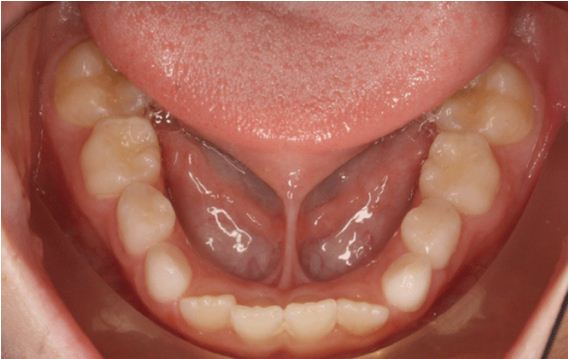

HÌNH ẢNH TRƯỚC VÀ SAU PHẪU THUẬT 01 NGÀY CỦA BN NGUYỄN ANH  NG. (9T) TẠI KHOA RĂNG HÀM MẶT – BVĐK TỈNH QUẢNG TRỊ

Thắng lưỡi là một nếp niêm mạc nối từ mặt dưới của lưỡi đến sàn miệng và xương hàm dưới. Thắng lưỡi bám thấp hay còn gọi là tật dính thắng lưỡi sẽ làm hạn chế hoạt động của đầu lưỡi. Dị tật này khiến trẻ nuốt khó khăn và hoạt động phát âm không hoàn thiện. Đối với trẻ sơ sinh, thắng lưỡi bám thấp cản trở vận động lưỡi, khiến trẻ bú khó, nuốt rất khó. Ở trẻ vào độ tuổi tập nói, dị tật này khiến trẻ chậm nói, nói ngọng và phát âm sai một số từ. Ngoài ra, thắng lưỡi bám thấp còn có thể gây một số bất thường trong quá trình mọc răng hàm dưới và sự phát triển của xương hàm. Nếu không được phát hiện điều trị kịp thời, dị tật này ảnh hưởng nhiều đến sự phát triển toàn diện của trẻ. Theo thống kê, có khoảng 5% trẻ sơ sinh gặp phải tật dính thắng lưỡi trẻ em và được phát hiện ngay trong tháng đầu sau sinh khi thăm khám sức khỏe định kỳ hoặc khi tiêm chủng.

- Răng cửa ở hàm dưới của trẻ bị hở hoặc nghiêng do dính thắng lưỡi.

- Vì tật dính thắng lưỡi khiến cho những răng cửa ở hàm dưới có khe hở hoặc bị nghiêng làm hàm răng trở nên mất thẩm mỹ.